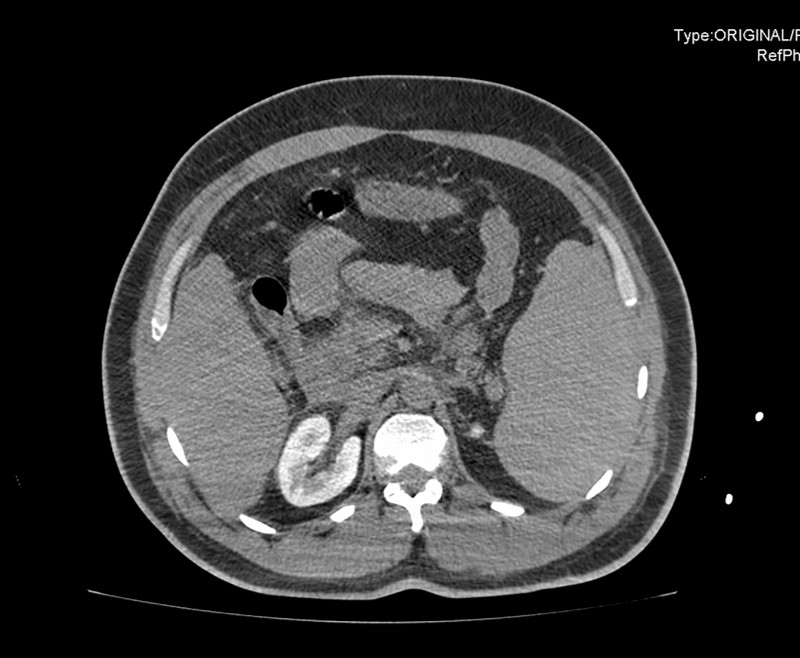

En base a estos hallazgos se realizó TAC (tomografía axial computerizada) de abdomen donde se confirmaron los signos de hepatopatía con hipertensión portal. Esplenomegalia y rotura contenida de bazo sin signos de hemorragia activa en el momento actual.

Inicialmente los síntomas del paciente y la microhematuria podrían orientar hacia un cólico renoureteral izquierdo. Comenzó con datos de coagulopatía que plantearon diagnóstico diferencial con microangiopatías trombóticas. Pero la trombocitopenia y la hipertransaminasemia unido a la esplenomegalia y el líquido libre en espacio esplenorrenal orientan a rotura esplénica que finalmente se confirmó en el TAC.